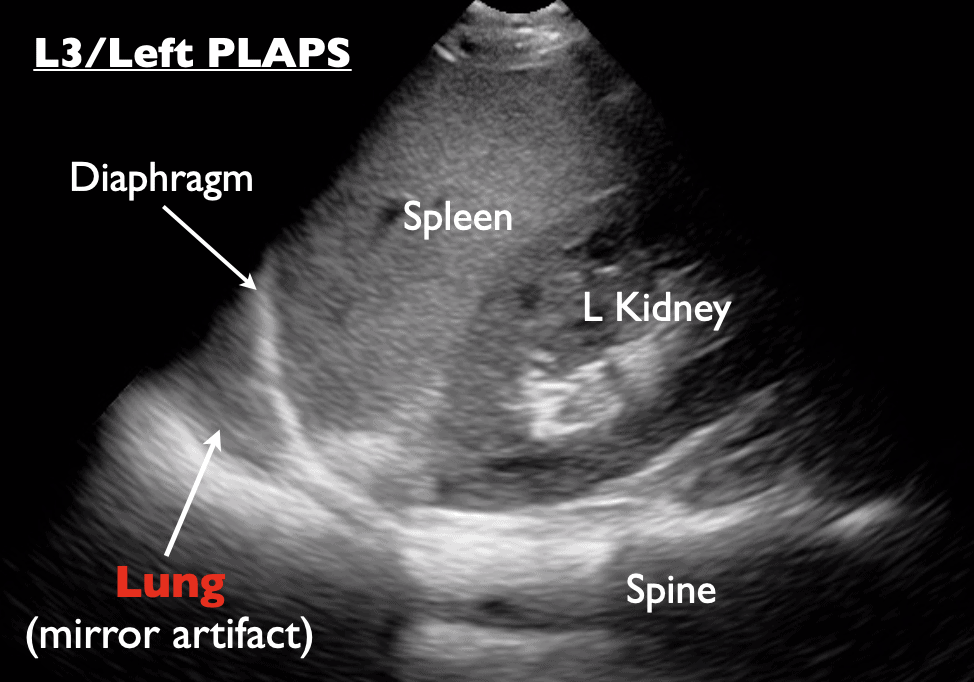

- Always use ultrasound to confirm you’re on the pneumothorax side and confirm you are above the diaphragm and no adhesions or vessels , mark with an X.